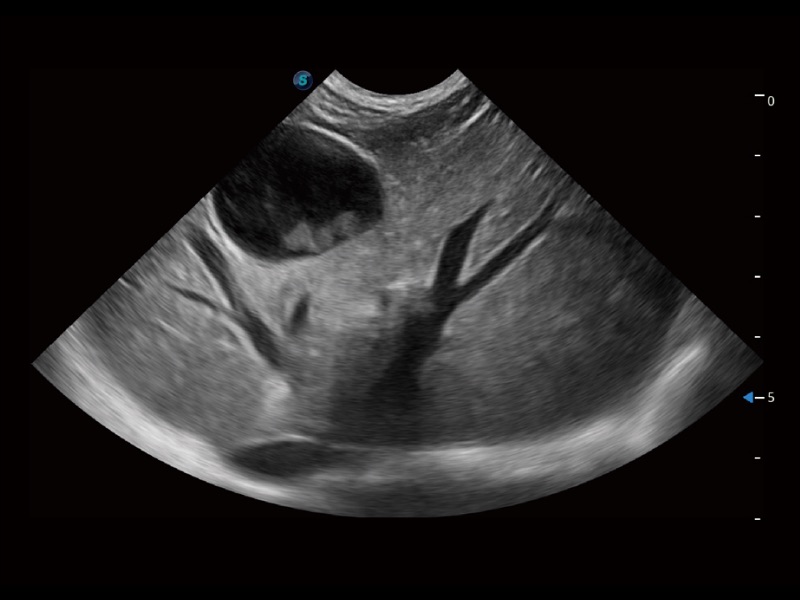

优异的基础图像

(猫)肺动脉血流频谱